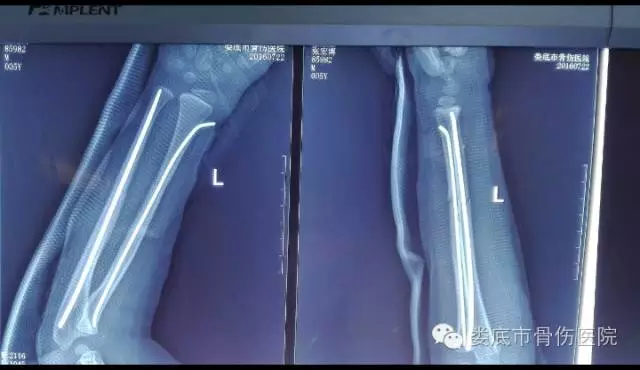

几天前的一个上午,当记者顶着炎炎烈日赶到娄底市骨伤医院骨外科病房时,龙龙小朋友打完点滴后,正准备出院了。前几日,龙龙小朋友还在家看电视,与兄弟玩闹,不慎从凳子上坠落,家人发现后立马把他送到了娄底市骨伤医院,经诊断为“左尺桡骨中段骨折”。

如果不是这突如其来的飞来横祸,或许此刻的他正在享受暑假的活蹦乱跳与欢声笑语,此次变故使龙龙小朋友的家人几近崩溃!医院专家考虑到小孩好动的特质和后期护理的难度,未对小孩采取传统的闭合手法及夹板外固定,而是采用了闭合复位弹性髓内钉固定的骨科微创术。仅用不到1小时手术时间就轻松解决了龙龙的骨伤问题,龙龙小朋友妈妈的脸上露出了久违的笑容。

据娄底市骨伤医院肩肘手足科副主任医师 彭放兵介绍:此类手术切口小,损伤小,长度只有一二公分,出血量少,仅20毫升,复位的稳定效果很好,很确定,基本不会出现再次移位变形的情况;而且愈合快,住院时间很短,几乎不要怎么用药,很快就可以出院,与传统术式相比,“短平快”优势明显。

(术后X光片)